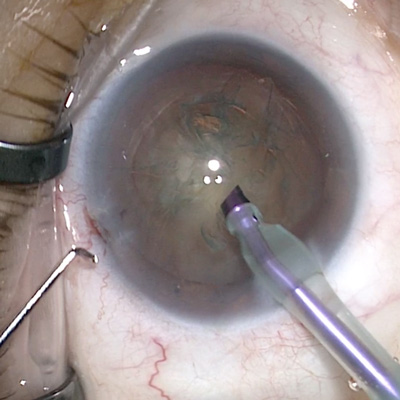

Cataract surgery in long eyes

Meeting the challenges that come with eyes of long axial lengths